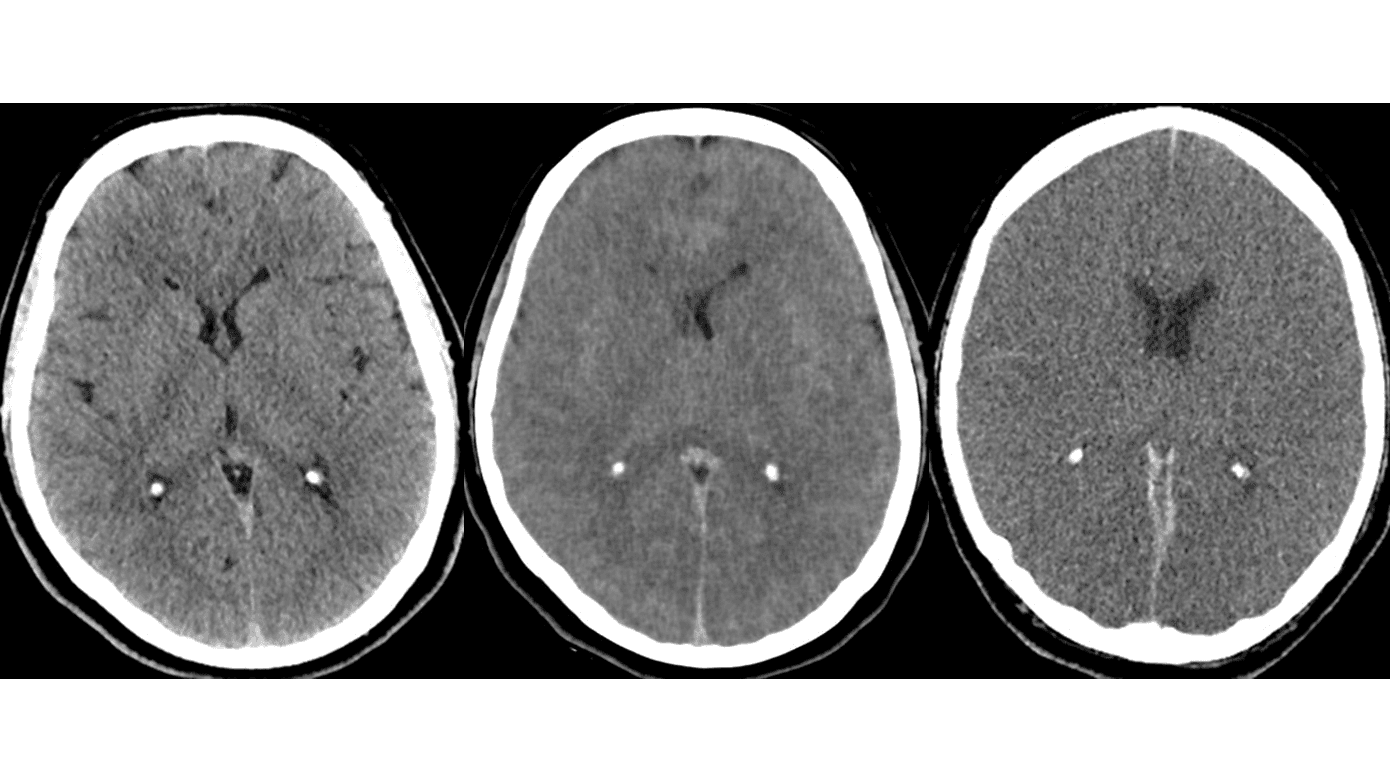

Før den kliniske hjernedødsundersøgelse kan foretages, skal en række forudsætninger være opfyldt (Tabel 1). CT af hjernen er den foretrukne undersøgelse, når årsagen til irreversibel hjernepåvirkning skal udredes (Figur 1). De tilstande, som »Bekendtgørelse om dødens konstatering ved uopretteligt ophør af al hjernefunktion« [13] omtaler som eksempler på årsager til uopretteligt ophør af al hjerneaktivitet, deles op i primære årsager, som omfatter: 1) blødninger i og uden på hjernen, 2) traumatisk hjerneødem og 3) primære hjernetumorer. De sekundære årsager omfatter påvirkning af blod- og iltforsyningen til hjernen, hvilket ses efter apopleksi, respirations- og hjertestop, kvælning, drukning eller længerevarende hypoperfusion.

I 1990 kunne CT-forandringerne i hjernen ved apopleksi samt respirations- og hjertestop ikke visualiseres med tilstrækkelig sikkerhed. Derfor blev det vanlig praksis at foretage en såkaldt opløbsangiografi i disse situationer. I dag er kvaliteten af CT af hjernen så god, at svære, hypoksisk-iskæmiske forandringer erkendes sikkert [18, 19], specielt når undersøgelsen gentages med 24 timers eller 48 timers interval.

Vi mener, at tiden er moden til en revision af hjernedødskriteriet fra 1990, og at behovet herfor er uafhængigt af, at der nu i Danmark foreligger mulighed for donation efter cirkulatorisk død. Styrelsen for Patientsikkerhed bør sammen med relevante videnskabelige selskaber som Dansk Neurologisk Selskab, Dansk Neurokirurgisk Selskab, Dansk Neuroradiologisk Selskab, Dansk Pædiatrisk Selskab og Dansk Selskab for Anæstesiologi og Intensiv Medicin stå for denne revision. En revision kunne bl.a. omfatte, at CT-forandringerne ved hypoksisk-iskæmisk hjerneskade accepteres som en irreversibel hjernepåvirkning [18, 19]. Den nuværende fremgangsmåde med to kliniske undersøgelser med apnøtest med en times mellemrum kan udfordres, ligesom alternativer til opløbsangiografi som f.eks. CT-angiografi bør overvejes (Figur 1 D-F). Endelig bør kriterierne for børn < 1 år fastsættes.

De danske hjernedødskriterier har ikke været revideret siden indførelsen i 1990. Den billeddiagnostiske udvikling gør, at CT-forandringer ved anoksisk-iskæmisk hjerneskade kan diagnosticeres sikkert, ligesom CT-angiografi vurderes at kunne erstatte DSA. En mere pragmatisk tilgang vil sandsynligvis kunne øge antallet af organdonorer og donerede organer uden at kompromittere den diagnostiske sikkerhed [15].